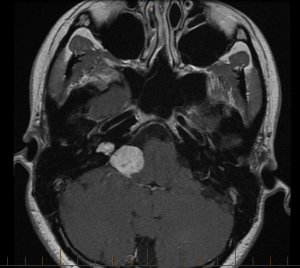

If you are in a similar boat then here are the details. Herbert is the ridiculous name attributed to my acoustic neuroma. He is approximately 3 cm and just leaning on my brainstem. All accounts point to Herbert being benign. Though I am lucky with my diagnoses, Herbert is causing me to evict him via brain surgery in December. Here I chronicle my story of Herbert, but also of me. I am the one living with him. I’m Samira. I’m 26, a PhD student studying women, violence and the media, hoping I can help find solutions to violence against women all around the world using new media tools and storytelling. Never underestimate the power of a good story. I am optimistic and happy to meet you!